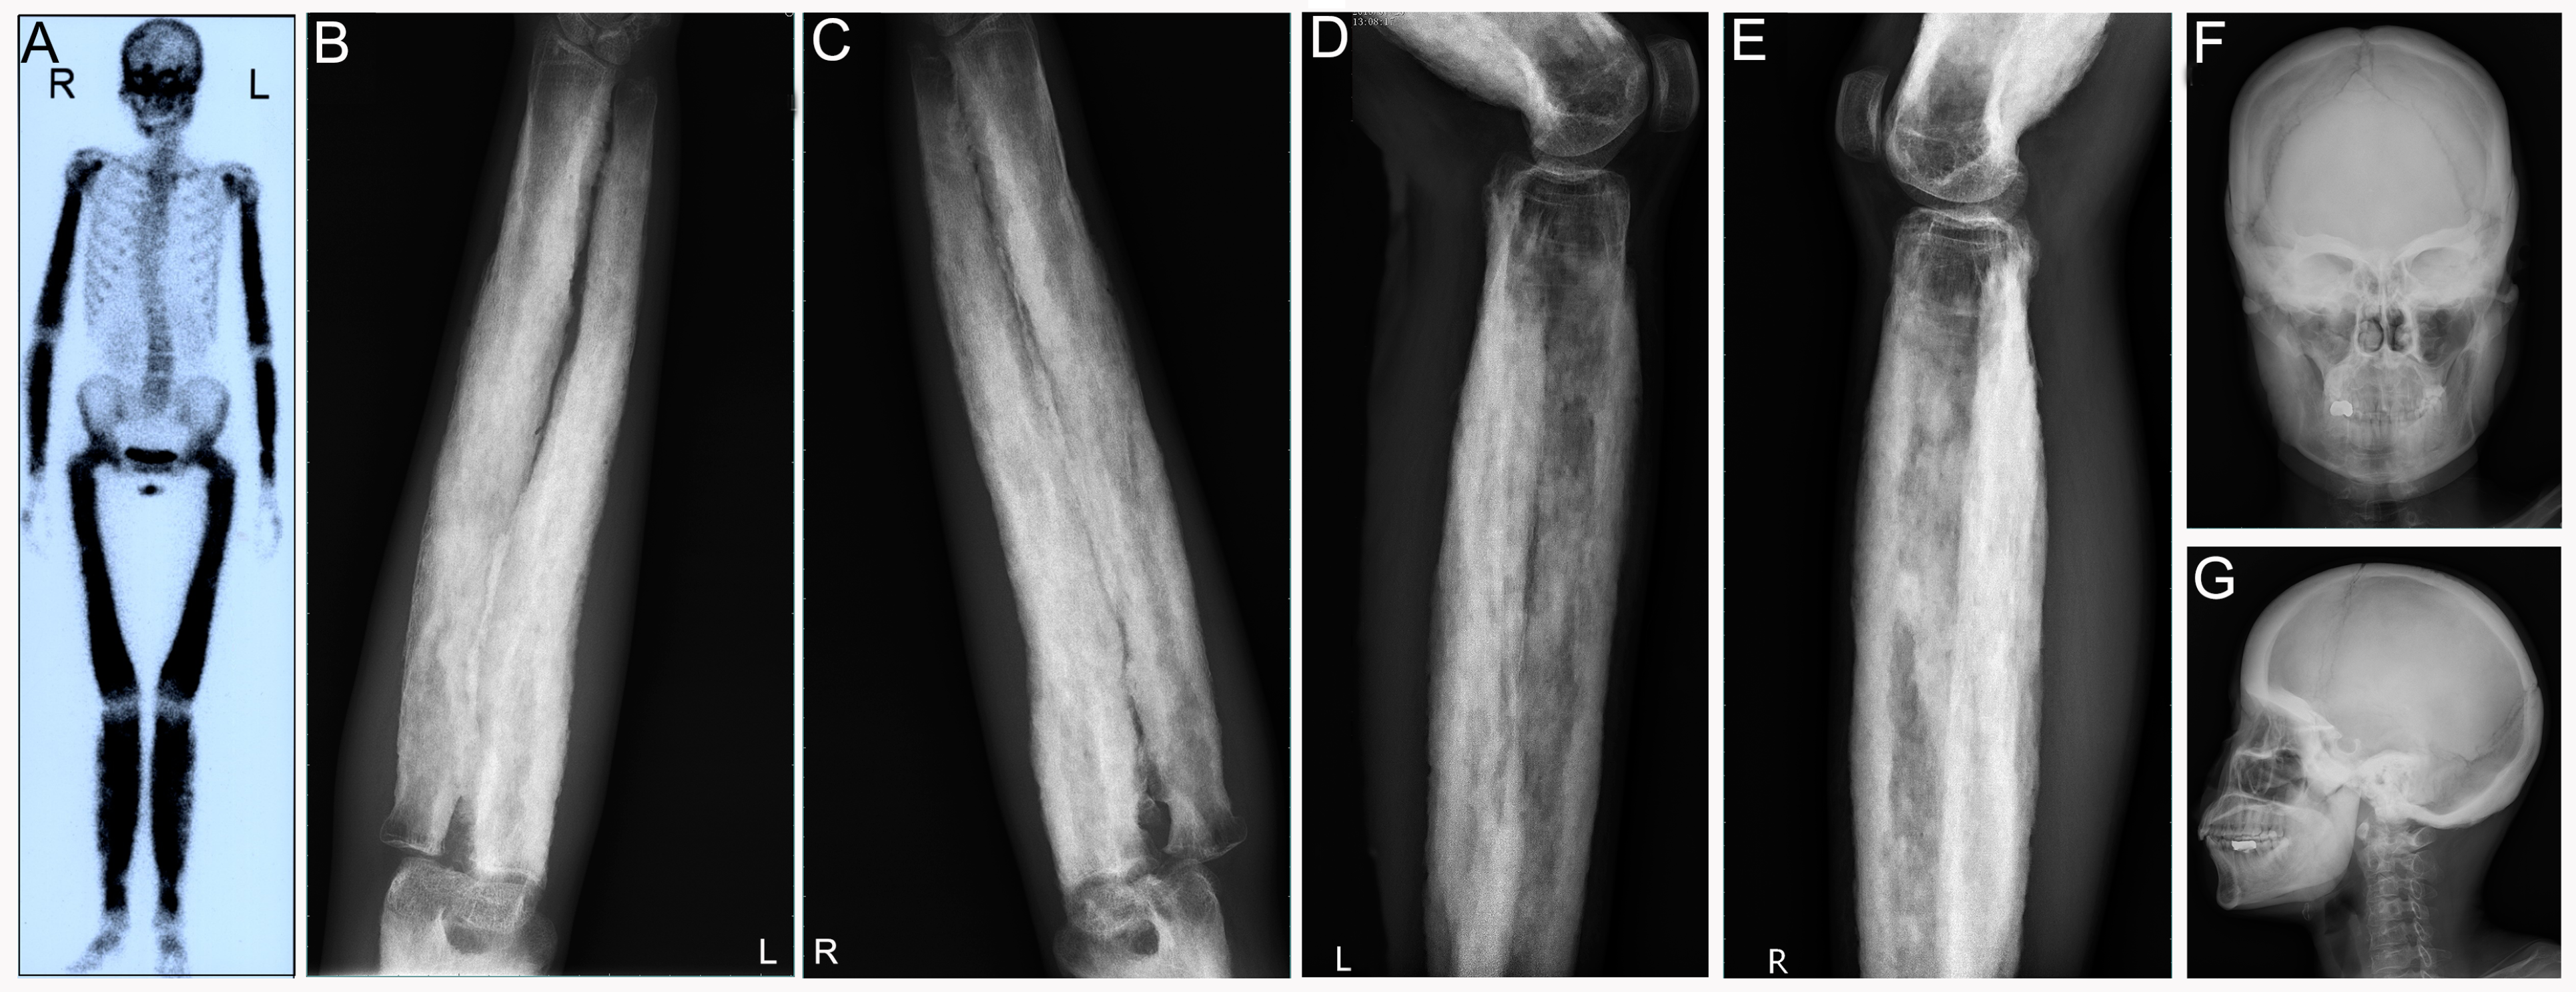

3.4. Progressive Diaphyseal Dysplasia (PDD)

3.5. Erdheim–Chester Disease (ECD)